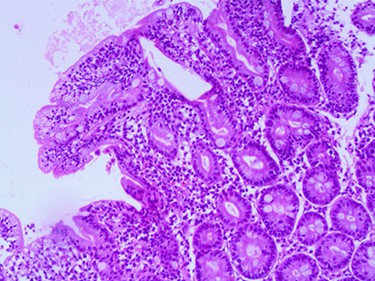

Compatible with Grade B2 on the new grading system for CD classification.

A 3.5-year-old Syrian female was admitted to our hospital with complaints of abdominal pain. She had had several episodes of non-bilious, non-bloody vomiting for 36 hours, and her last normal bowel movement was 2 days prior. Although the patient had a history of sickle cell anemia confirmed by electrophoresis from her first year of life, she had not experienced any sickle cell crises and had not needed blood transfusion or hospitalization. She had no history of diarrhea, either. Family history for celiac disease was positive in a second-degree relative. On admission, her vital signs were normal. Blood analysis indicated low hemoglobin (Hgb) concentration of 9.3 g/dl, but other initial laboratory results were normal. Abdominal examination showed tender distended abdomen. Abdominal ultrasonography suggested the presence of intussuscepted bowel in the right iliac fossa with free fluid between the bowels. Hydrostatic reduction (HR) was not successful, so she underwent surgical reduction. Although no lead points were found, there were multiple enlarged mesenteric lymph nodes and edematous ileocecal junction. On the third postoperation day, the patient again developed similar symptoms, and this time ultrasonography revealed IS in the left side of the abdomen. There was no improvement in symptoms for 24 hours, and ultrasonography revealed the same results after an HR attempt. The patient was operated on a second time, and manual ileoileal IS (Fig. 1) reduction and prophylactic appendectomy were performed. The postoperative course was uneventful, and the patient was discharged 3 days later. Three months later, the patient developed abdominal pain, and the diagnosis of IS was confirmed via ultrasonography. This time, IS reduced over 24 hours of observation. As no lead point was found through the later laparotomy, further investigations were conducted. Upper gastrointestinal endoscopy was performed and showed a mosaic pattern of the duodenum mucosa suggestive of CD. On microscopic evaluation, sections reveal advanced atrophy of duodenal villi with occasional intraepithelial lymphocytes (>30/100 IEL). Crypts show moderate hyperplasia; the lamina propria is infiltrated by diffuse mononuclear inflammatory cell infiltrate. Histopathologically, it is compatible with Grade B2 on the new grading system for CD classification (Figs 2–4). The child was then administered with a gluten-free diet. Eight months later, she visited the hospital as outpatient, and examination revealed she was free of any symptoms.